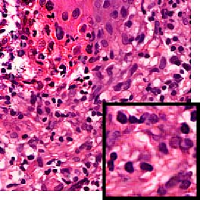

Leishmaniasis background and histology presentation. The World Health Organization (WHO) has selected cutaneous leishmaniasis as a neglected tropical disease (NTD) with growing, uncontrolled, and ignored infection affecting millions of people every year [14, 9]. It is unfortunately one of the world’s most neglected poverty-related diseases, affecting the poorest people in developing countries and it is associated with risk factors like malnutrition, immune system deficiency, migration, inadequate education, illiteracy, gender inequality, and a shortage of services [1]. Furthermore, only eight countries in the world contribute to 90% of leishmaniasis cases: Afghanistan, Algeria, Brazil, Iran, Pakistan, Peru, Saudi Arabia, and Syria [12]. It is a vector-borne infection caused by the protozoan parasite Leishmania. The vector is the female sand-fly. The lesions of cutaneous leishmaniasis vary in presentation ranging from a single self-limited skin lesion to multiple large destructive and ulcerated lesions on mostly the exposed parts of the body such as face, forearms, and lower legs [2]. Skin biopsy is considered the gold standard method for confirmation of diagnosis. The presence of large epitheloid granulomas and small hematoxylinophilic LD bodies (that are round, uniform in appearance, intracytoplasmic and sometimes distributed around the outer rim of the vacuoles) is critical for diagnosis and confirmation of leishmaniasis [4]. Large granulomas are visible at 10X but the smaller hematoxylinophilic bodies (around 3-4mm in size) are usually visible at 40X and can easily be missed if they are few in number, leading to misdiagnosis. Specialized dermatopathologists are the only ones who can diagnose these accurately based on patient history, clinical features, and laboratory diagnosis. It is thus critical to share the digitized slides of these cases from rural poor remote areas with dermatopathologists (mostly residing in urban centers) for quick diagnosis and accurate management of the patient.

We demonstrate our WSI creation workflow on Leishmaniasis cases, as shown in Figures 1 and 4. An expert pathologist reviewed the cases and annotated granulomas as well as LD bodies on the stitched images and our generated images in Figure 4. To show generalizability of our approach, we also show results on core biopsies of breast, duodenum, stomach, liver, and lymph nodes (Figure 5).